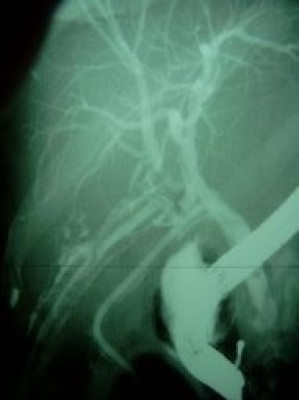

Lesión de conducto hepático derecho post colecistectomía

Envíado por Dr. Carlos Miguel Zavaleta Consuegra